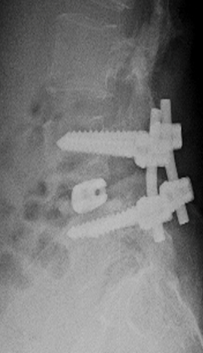

At presentation she had severe paraspinal spasm with movement restriction and no neurological deficits. Radiographs revealed a minimal reduction in L4/5 disc space . Hematological evaluation elevated showed TLC, ESR, CRP. MRI showed evidence of discitis at L4/5 with adjacent vertebral reactive changes( FIG 1,2). With a working diagnosis of post partum spondylodisctis she underwent a septic screening ( sputum, urine, blood cultures) and a CT guided biopsy which turned out to be negative. Considering her significant back pain  with limitations in suggesting antibiotics  she was suggested surgical debridement and fusion at L4/5. She underwent PLIF L4/5 under GA and had a drastic early pain relief . She was mobilized on post operative day – 1 with lumbo sacral brace. Her pain reduced significantly ( VAS 2/10) which needed minimal analgesics ( once a day paracetamol 1 gm intravenous infusion )for 5 days . She was able to turn in bed and sit to nurse the child. Her intraoperative tissues sent for culture grew pseudomonas which was sensitive to cefaperazone + sulbactum. She was initiated on intravenous antibiotics for 2 weeks duration and was followed up with further 4 weeks of oral antibiotics . Radiographs revealed fusion at L4/5 at 3 months( FIG 3,4) of follow up with serological markers normalizing by 6 weeks.

Fig 3: L4/5 PLIF- AP view

Fig 4: L4/5 PLIF- Lateral view